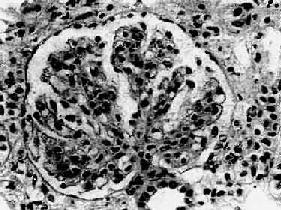

图12-13 膜性增生性肾小球肾炎 肾小球系膜细胞增多,增生的系膜组织侵犯毛细血管,毛细血管壁增厚,腔狭小,肾小球丛呈分叶状 电镜观察可见肾小球系膜增生,毛细血管基底膜不规则增厚。增生的系膜组织沿毛细血管基底膜和内皮细胞之间向毛细血管周围部分伸展,甚至环绕全部毛细血管壁,使毛细血管壁增厚。肾小球内有大量电子致密物沉积。根据沉积物的部位,可将膜性增生性肾小球肾炎分为3型: Ⅰ型电子致密物沉积在肾小球基底膜内侧,内皮细胞下,大小不等,常聚积成大团块状(图12-14,图12-15)。系膜内和上皮细胞下偶然也可见有少量小而不规则的沉积物。